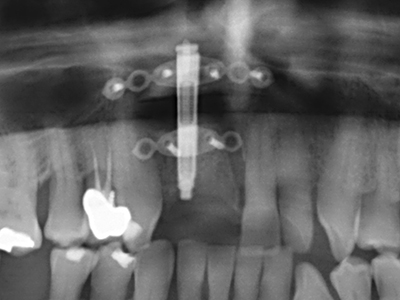

As noted above, indications for piezosurgery can also be found in the field of conservative dental surgery. Special working tips simplify the exposure of root tips and make it easier to protect nerves and sinus mucous membranes, particularly in the lower premolar and upper posterior tooth regions. Angled diamond tips are used to precisely prepare the resection cavity for the retrograde root filler material for unsealed apical obturation. The ultrasonic technology means the tips can be very slender, which improves the view and the size of the access cavity. As a result, the application of ultrasonic surgery for this indication is one of the standard procedures for apical resection (Del Fabbro, Tsesis et al. 2010, Scarano, Artese et al. 2012).

Indication: Apical resection